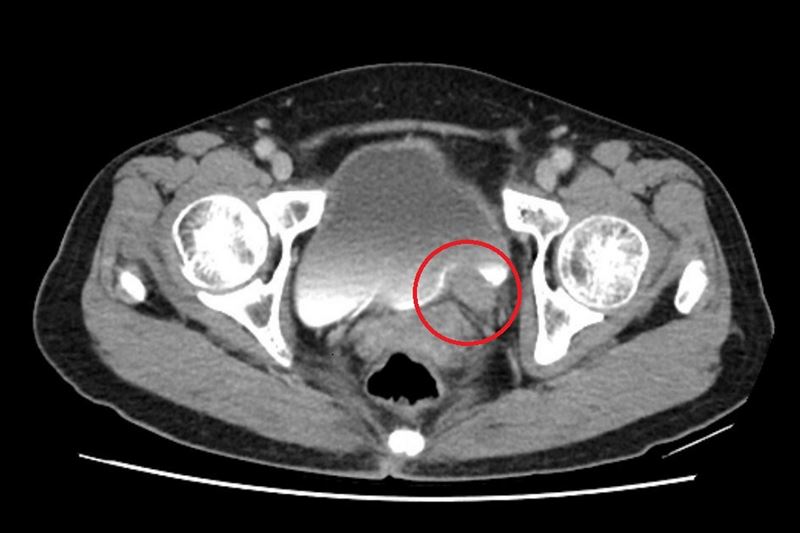

67歲的林女士一向健康,卻在近期出現間歇性的無痛血尿,她原本以為只是小問題,至醫院檢查後,竟發現左側輸尿管末端長了一顆5公分的腫瘤,並造成腎水腫情形。確診為輸尿管泌尿上皮癌後,醫師先安排化療縮小腫瘤,再利用達文西手術切除腫瘤並重建輸尿管,成功保留腎臟功能,林女士術後追蹤至今,病情控制良好。

台北慈濟醫院泌尿科醫師許竣凱表示,輸尿管是連接腎臟與膀胱的重要管道,負責將腎臟產生的尿液順利輸送到膀胱儲存與排出。根據衛福部統計,泌尿上皮癌發生率每十萬人中約有40-50例,臨床上,醫師會以尿液檢驗、膀胱鏡、超音波與電腦斷層進行診斷,排除泌尿道感染、輸尿管結石等會伴隨疼痛的血尿後,就要高度懷疑腫瘤的可能。